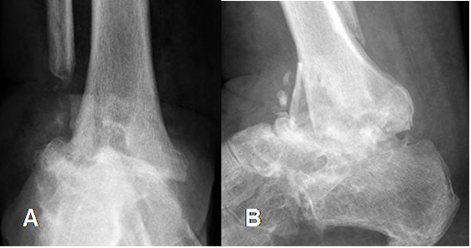

Fig 131. Artropatía neuropática en fase crónica.

A: Rx AP y B: Rx lateral del tobillo. Postquirúrgico de fractura del tobillo. Pérdida del espacio articular tibioastragalino, esclerosis, reabsorción ósea y subluxación.